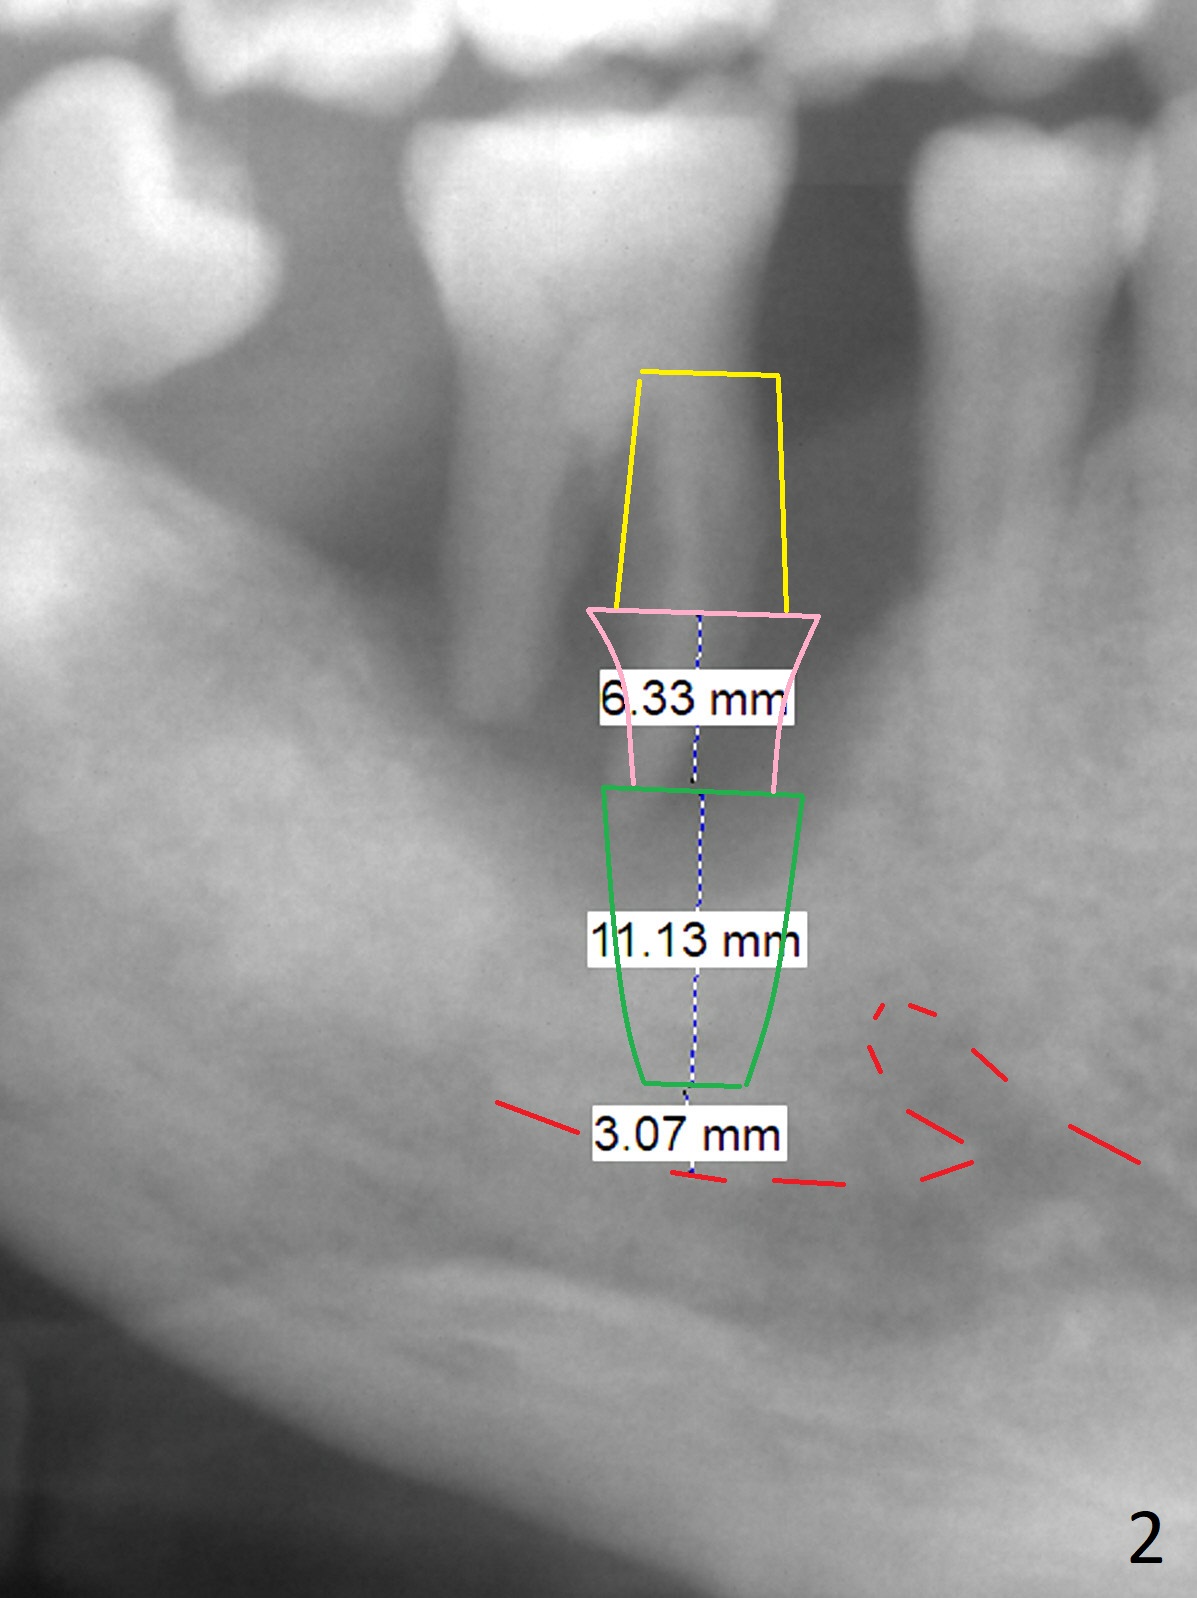

A 57-year-old man has advanced periodontitis with bruxism. The mobile teeth #13 and 30 are his main concern (Fig.1). The tooth #30 has shifted distally. An implant will be placed in the mesial socket, if present. Due to severe bone loss, a 7 mm long abutment with 6 mm cuff is most likely to be used (Fig.2). Since the socket is huge, prepare large piece of gauze for hemostasis. Osteotomy should be initiated as buccal as possible, as the Inferior Alveolar Canal is near the lingual plate at the 1st molar. Prepare Sinus Master Kit. Why? Always take PA after initial drill to avoid violating the Canal. It may be ok to see the overlapping between the parallel pin and the Canal. Do not administer the Inferior Alveolar nerve block.